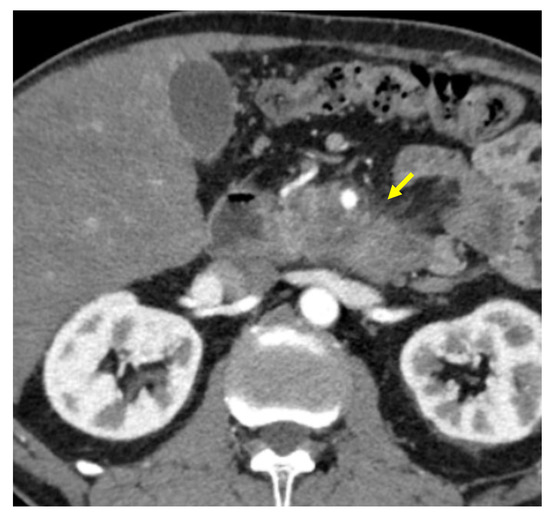

Tumor margins showed a significant difference in the two groups, appearing well-defined in only 6 (6.98%) metastatic patients and ill-defined in the remaining 80 (93.02%); in the non-metastatic group, the margins appeared well-defined in 132 (65.35%) and ill-defined in 70 (34.65%) tumors (Figure 2, Figure 3, Figure 4 and Figure 5).

Figure 2. Pancreatic lesion with well-defined margins (arrow) on CT examination in pancreatic contrast phase.